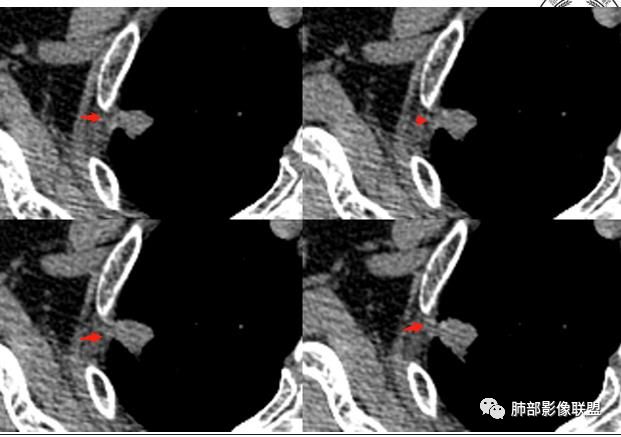

2.右肺尖类圆形结节影,边界清楚,未见明显分叶或深切迹,部分分边缘较平直,可见细长毛刺棘状突起,相邻胸膜增厚,未见胸膜凹陷。后段胸膜下见条索影及微小结节影。

相关血管未见脐凹,有限图像层面未能显示相关支气管情况。

3.平扫病灶密度密度不甚均匀,外侧份见微小高密度影。

好发于肺尖或尖后段胸膜下的密度不均的结节什么病最常见?结核!

小病灶常常出现空洞的什么病最常见?结核!

空洞内外壁都很清楚的什么病最常见?结核!

周围伴随小结节及条索影的什么病最常见?结核!